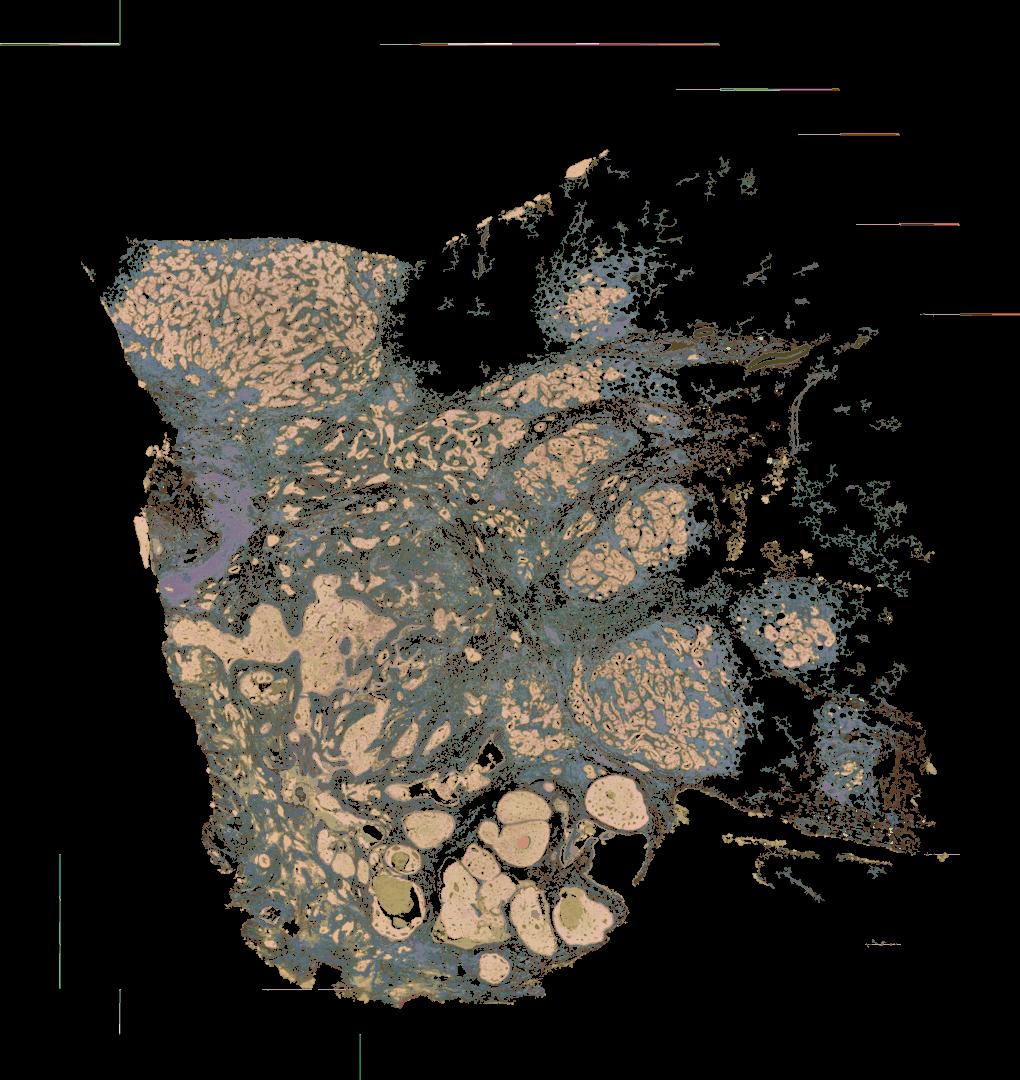

To study the spatial interactions among cancer and non-cancer cells1, we here examined a cohort of 131 tumour sections from 78 cases across 6 cancer types by Visium spatial transcriptomics (ST). This was combined with 48 matched single-nucleus RNA sequencing samples and 22 matched co-detection by indexing (CODEX) samples. To describe tumour structures and habitats, we defined ‘tumour microregions’ as spatially distinct cancer cell clusters separated by stromal components. They varied in size and density among cancer types, with the largest microregions observed in metastatic samples. We further grouped microregions with shared genetic alterations into ‘spatial subclones’. Thirty five tumour sections exhibited subclonal structures. Spatial subclones with distinct copy number variations and mutations displayed differential oncogenic activities. We identified increased metabolic activity at the centre and increased antigen presentation along the leading edges of microregions. We also observed variable T cell infiltrations within microregions and macrophages predominantly residing at tumour boundaries. We reconstructed 3D tumour structures by co-registering 48 serial ST sections from 16 samples, which provided insights into the spatial organization and heterogeneity of tumours. Additionally, using an unsupervised deep-learning algorithm and integrating ST and CODEX data, we identified both immune hot and cold neighbourhoods and enhanced immune exhaustion markers surrounding the 3D subclones. These findings contribute to the understanding of spatial tumour evolution through interactions with the local microenvironment in 2D and 3D space, providing valuable insights into tumour biology.